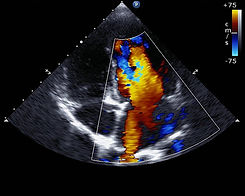

Echocardiography